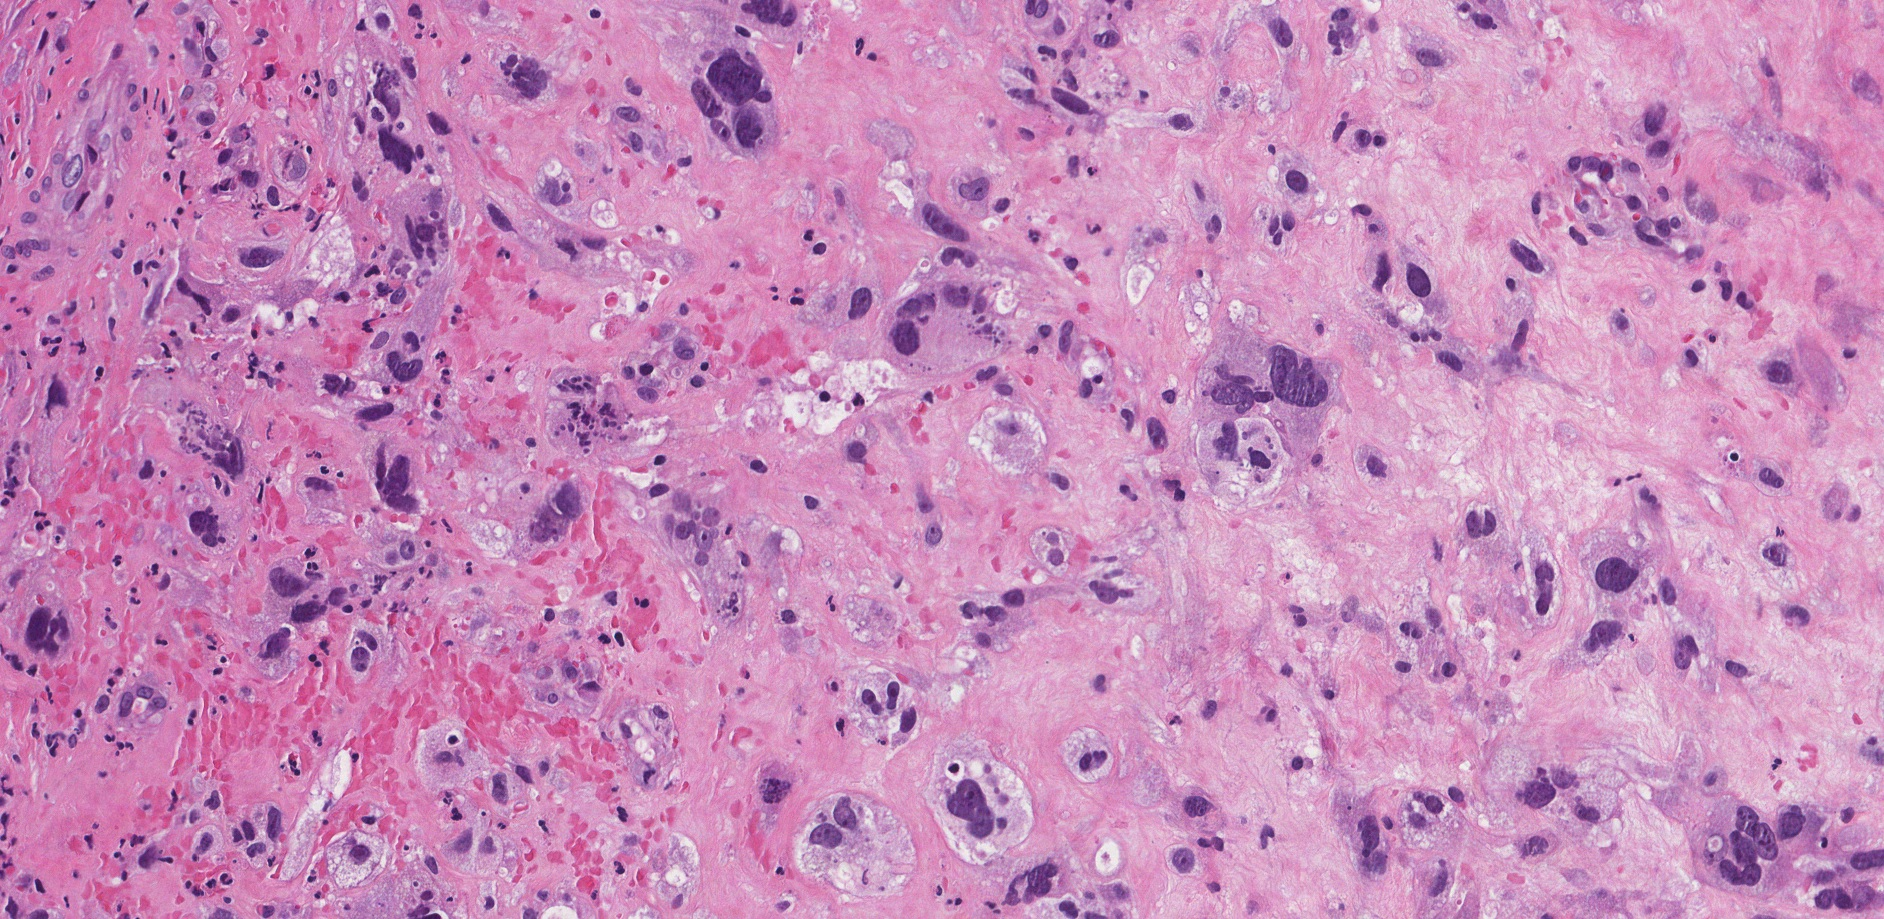

cytologic atypia